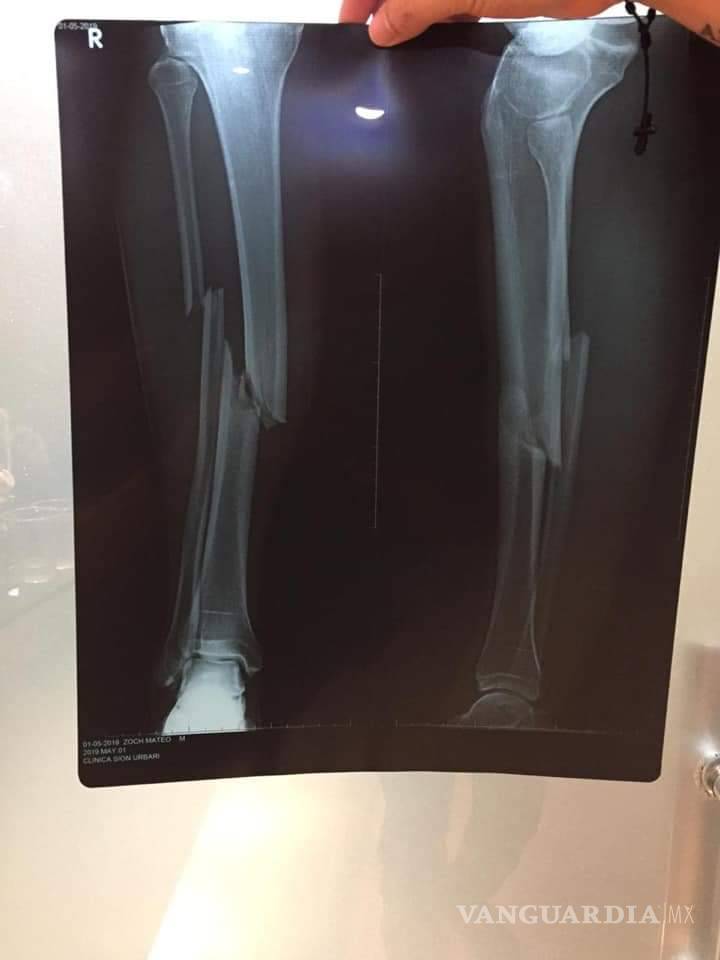

Mateo Zoch enfrenta fractura de tibia y peroné tras haber sido barrido por su rival, Leonardo Urapuca

Una escalofriante lesión se presenció en Bolivia cuando Leonardo Urapuca, del Blooming, le dio una fuerte entrada a Mateo Zoch, del Royal Pari, lo que resultó en doble fractura para el agraviado.

Corría el minuto 78, el marcador iba 2-2, y en un balón dividido, Urapuca le llegó a Zoch con los tacos de frente, provocando ruptura de tibia y peroné al mediocampista boliviano.